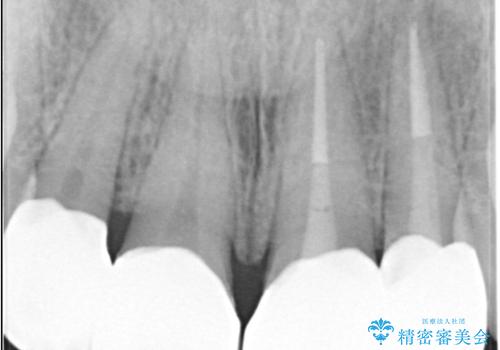

- 上顎の前歯4本が、過去の治療痕による変色や欠けで見た目が気になるとの主訴でご来院されました。患者様は、思い切り笑えるよう自然で美しい前歯を求めていらっしゃいました。そこで、最も天然歯に近い審美性を再現できるオールセラミッククラウンを用いた治療計画を立案しました。歯並びや色のバランスを整え、長期的に安定する美しい口元を獲得することを目指します。

治療はまず、審美性を最大限に高めるために、歯肉のラインや前歯の形を整えることから始めました。その後、4本の歯を丁寧に形成し、金属を一切使用しないオールセラミッククラウンを作製しました。